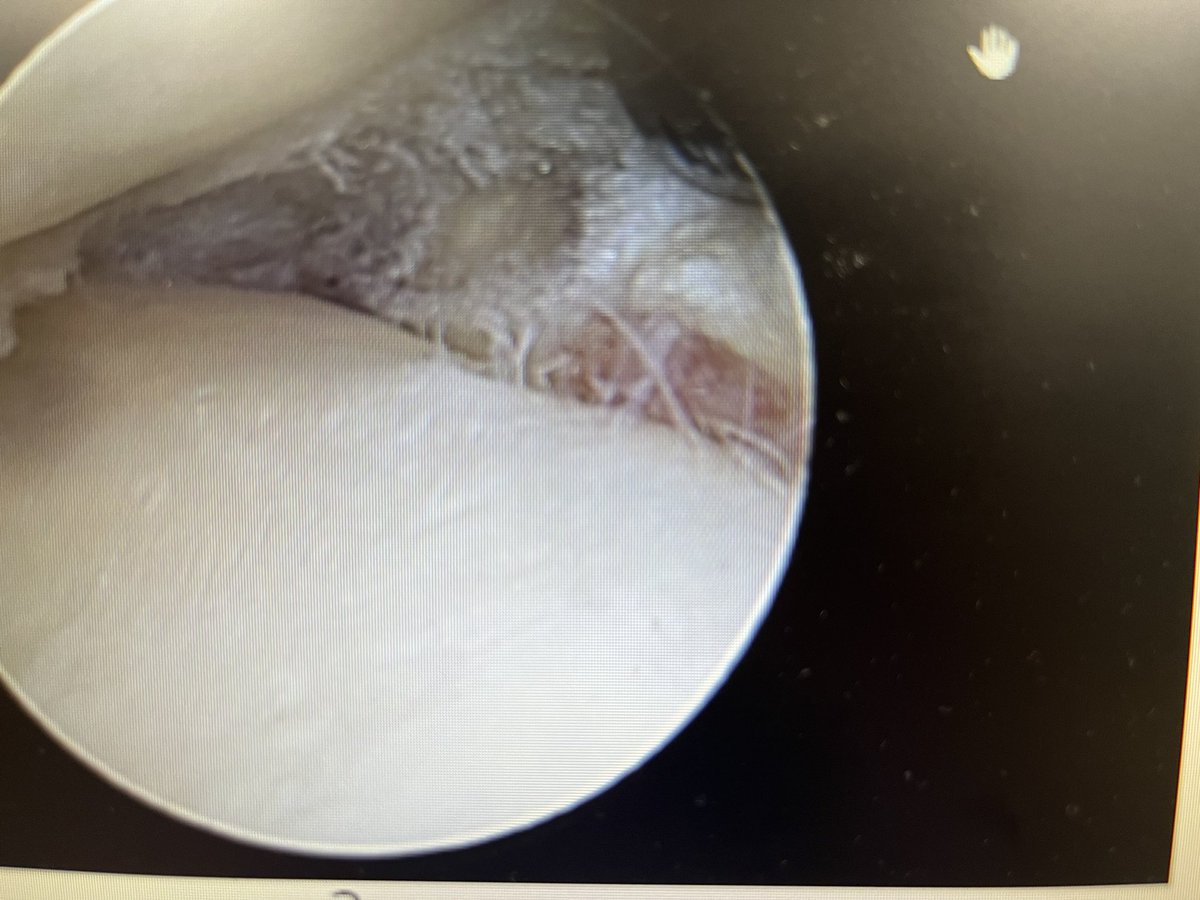

After resection what I consider a good prognostic sign. There is synovitis ( redness) on the capsule adjacent to where the meniscus has been causing pain.might pain and symptoms tend to settle very rapidly in these patients.

Jonathan Bell tweet media